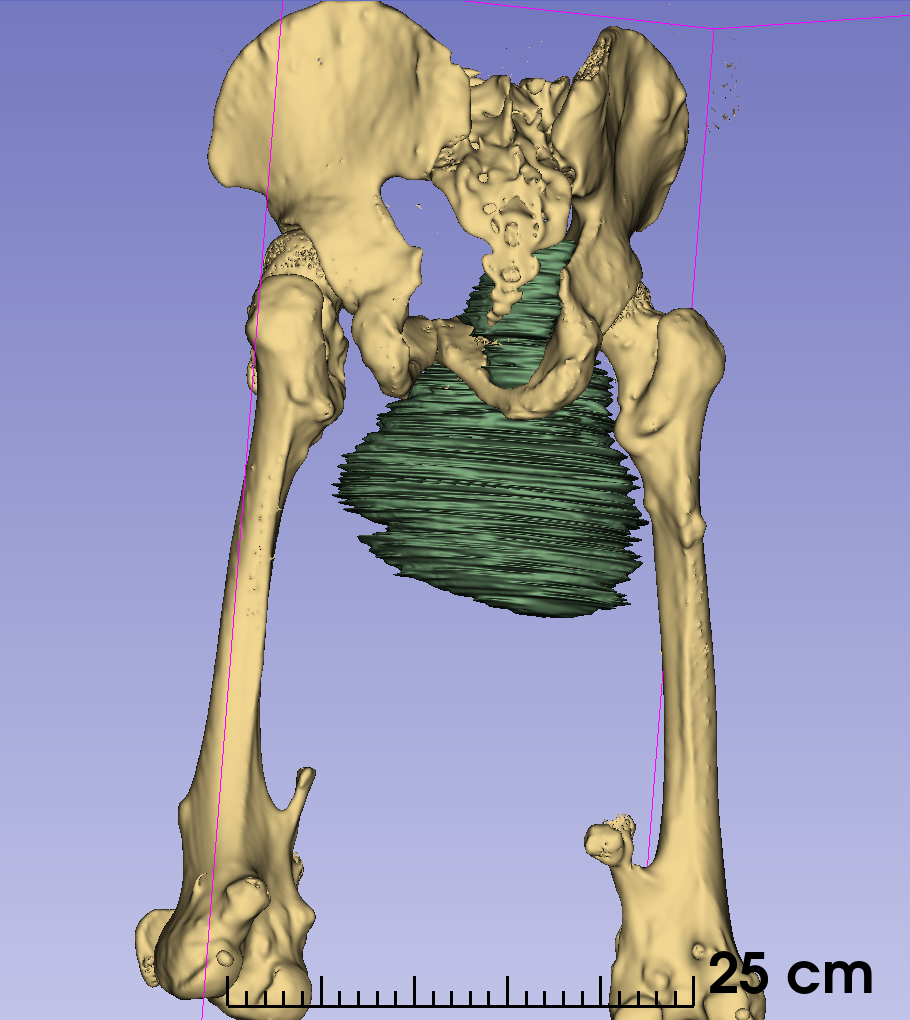

通过3D建模的精准评估,小王右耻骨软骨肉瘤体积达到了1600立方厘米(1600623.71立方毫米),肿瘤下极自右大腿中段向上,内侧贴大腿皮肤,外侧推压内收肌群及股动静脉,穿过骨盆右闭孔,紧贴右髋臼内侧壁生长,骨盆内占位部分推压膀胱。

图片 7.png

软件测算肿物体积

图片 8.png图片 10.png图片 9.png

3d建模

患者的肿瘤累及右侧耻骨上下支(Enneking Ⅲ区),预计截骨范围为耻骨联合到耻骨上支、耻骨下支到坐骨体内侧。由于肿物体积巨大,无论采用髂股入路还是髂腹股沟入路,单纯前路手术很难暴露坐骨及髋臼后柱结构,而在前路强行提拉推压肿物则会增加肿瘤破裂的风险。通过延伸Gibson入路,可以清晰的显露坐骨支,完整地显露截骨边界,降低肿瘤破裂及血管损伤的风险。由于该部分区域为非负重区,因此,无需进行骨盆环重建,但需要注意盆壁的修补,预防盆腔器官受重力作用下垂相关并发症。